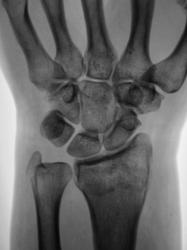

Пациент направлен врачом общей практики (ВОП) на рентгенографию лучезапястного сустава с диагнозом "Перелом?". Произведено стандартное исследование лучезапястного сустава. Выявлен перелом лучевой кости в типичном месте почти без смещения отломков, перелом локтевой кости в области основания шиловидного отростка с незначительным смещением отломков по ширине. Возникает подозрение на разрыв дистального луче-локтевого сочленения. Ваше мнение коллеги?